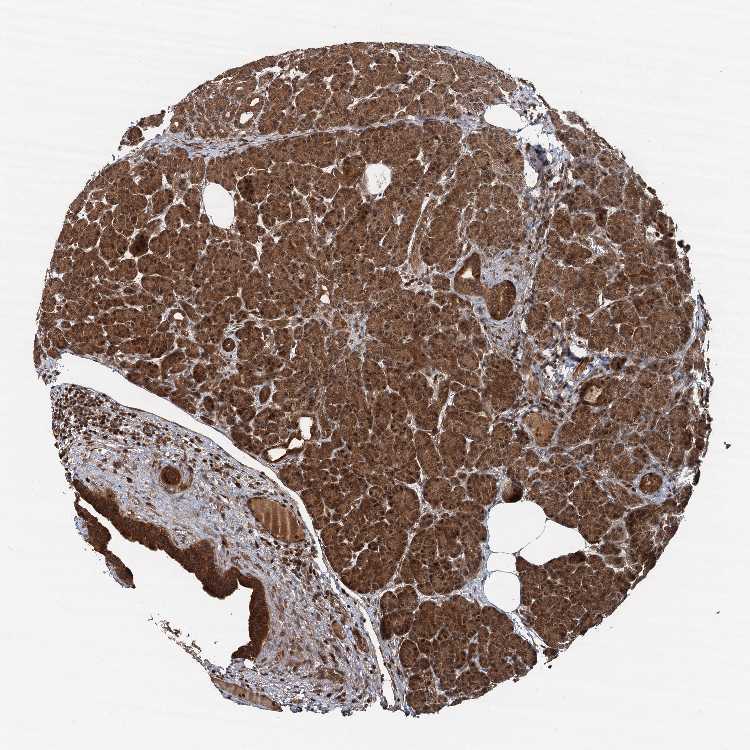

PANCREAS - Antibody stainingi

Antibody staining in the annotated cell types in the current human tissue is reported as not detected, low, medium, or high, based on conventional immunohistochemistry profiling in selected tissues. This score is based on the combination of the staining intensity and fraction of stained cells.

Each image is clickable and will lead to virtual microscopy that enables deeper exploration of all samples and also displays staining intensity scores, fraction scores and subcellular localization as well as patient and tissue information for each sample.

Antibody HPA041222Antibody HPA043531Antibody CAB037202Antibody CAB037209

Exocrine glandular cells LowLowHighHigh

Pancreatic endocrine cells Not detectedLowHighHigh